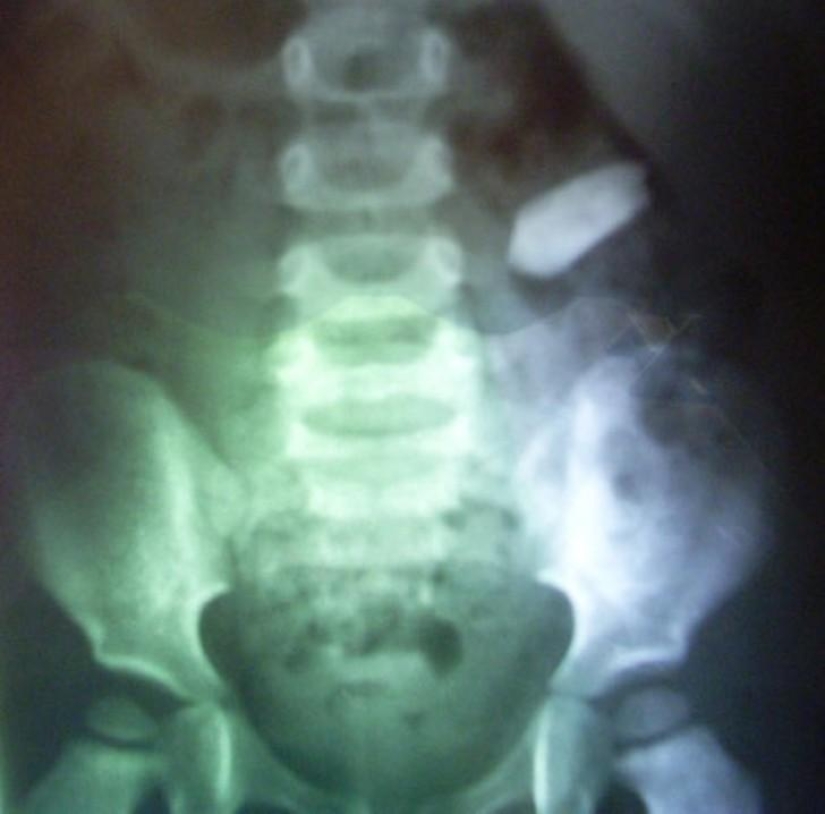

Spoon.